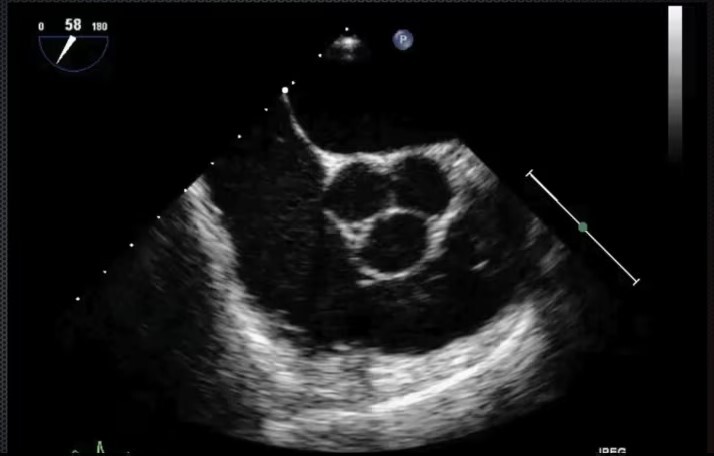

Mid-Esophageal Aortic Valve Short Axis View - LA, RA, RV, tricuspid valve, pulmonic valve, aortic valve. Advance probe from MEAscAoSAX until you can see it.